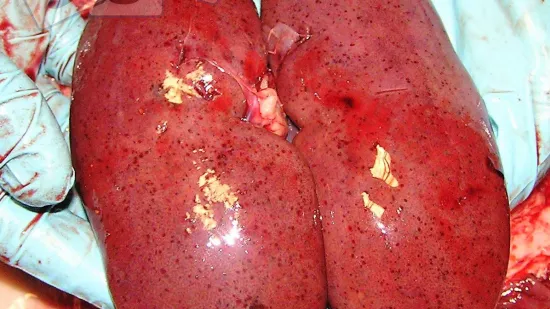

以下哪个可能是造成脾肿大的原因?